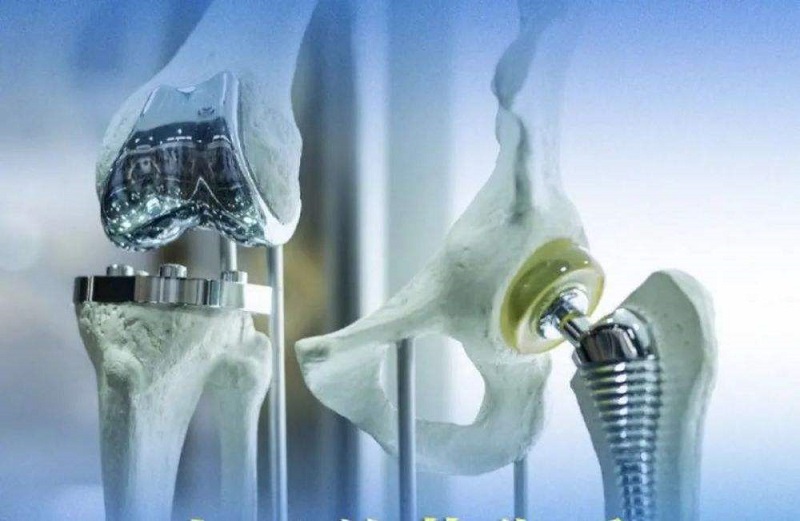

關(guān)節(jié)類植入物產(chǎn)品主要指實(shí)現(xiàn)因關(guān)節(jié)周圍骨折、累計(jì)關(guān)節(jié)的骨腫瘤及其他原因引起的骨缺損等關(guān)節(jié)障礙的關(guān)節(jié)功能重建的人體植入物,主要產(chǎn)品可分為人工膝關(guān)節(jié)、髖關(guān)節(jié)和肩關(guān)節(jié)以及小關(guān)節(jié)等。